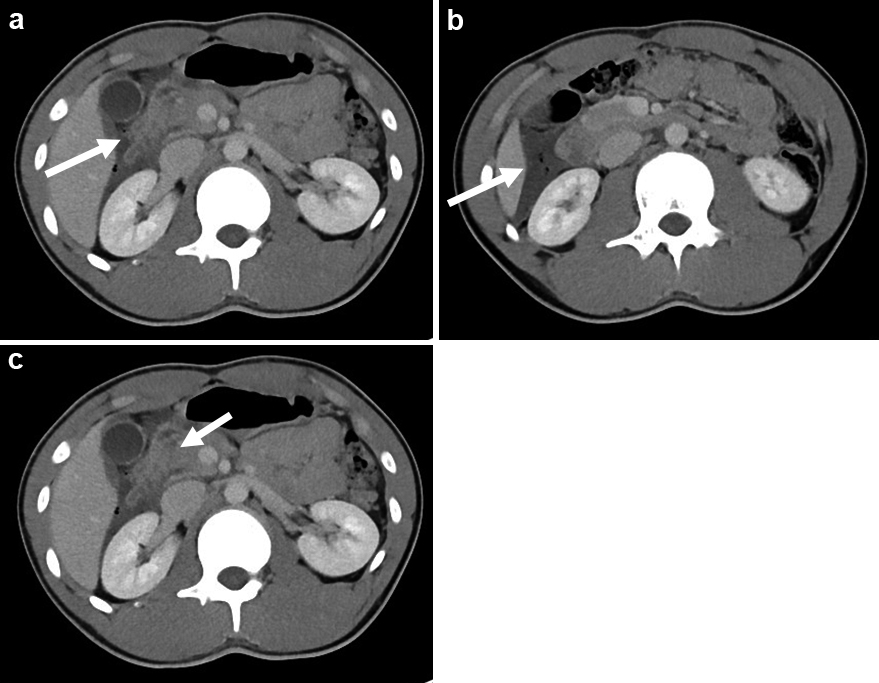

腹部ダイナミックCT所見:十二指腸下行脚に管腔構造の不明瞭化を認め(Fig. 2a),同部より外側にガス像を含む液貯留を認めた(Fig. 2b).膵頭部には断裂を疑う所見を認め,周囲脂肪織濃度の上昇を認めた(Fig. 2c).

Abdominal CT. a: The lumen structure of the second part of the duodenum is unclear. b: The arrow shows fluid and air collection. c: The pancreatic head was suspected of rupture, and the concentration of surrounding fat tissue is elevated.